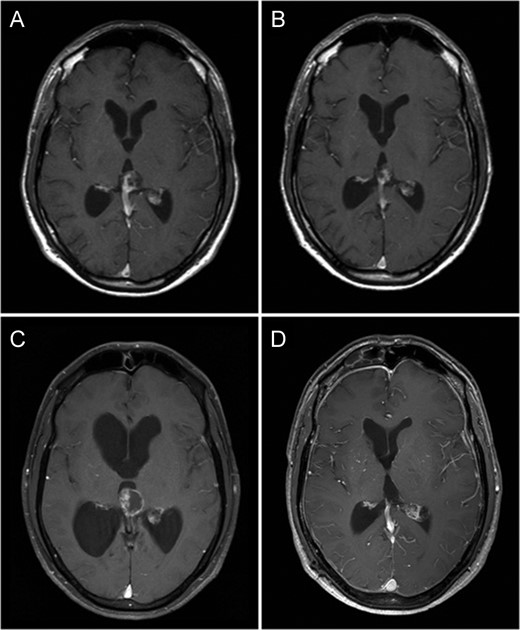

Fat saturated axial gadolinium enhanced T1 weighted MR Brain Image Series (A—July 2000, B—October 2003, C—July 2009 and D—November 2010). Image A demonstrates a heterogeneously enhancing lesion involving the pineal gland with enhancing solid as well as cystic components. Image B demonstrates a reduction in size of this lesion following radiation therapy. Image C demonstrates a prominent increase in the cystic component of the lesion associated with obstructive hydrocephalus. Image D demonstrates no residual tumour or contrast enhancement 1-year following surgery.

The patient received 50 Gy/28 fractions of whole brain radiation therapy, which corresponded with reduction in size of the mass. He made an excellent recovery with complete resolution of his symptoms. He was kept under radiological surveillance for a period of 5 years with no signs of progression (Fig. 1B).

Nine years after his initial presentation, the patient represented with worsening headache, staggering gait and mild memory impairment. Imaging revealed an increase in size of the pineal mass, with a marked enlargement of the cystic component, associated with extension into the third ventricle and obstructive hydrocephalus (Fig. 1 C).